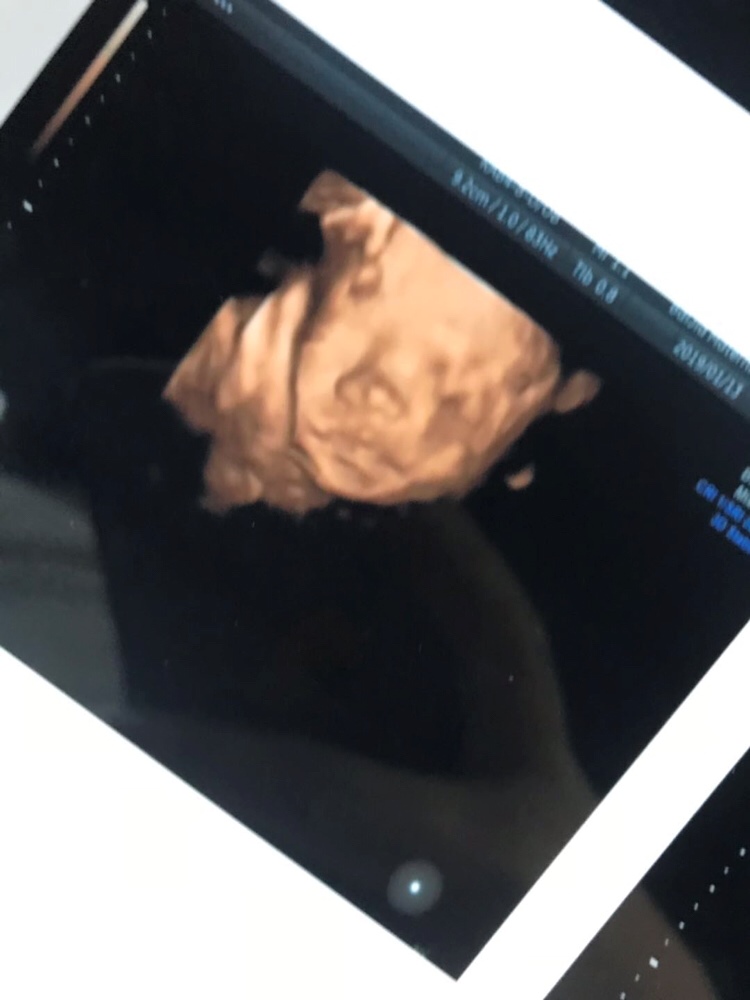

宝宝3天

四维你是啥时候做的

张素陌[帖主]:六个月的时候